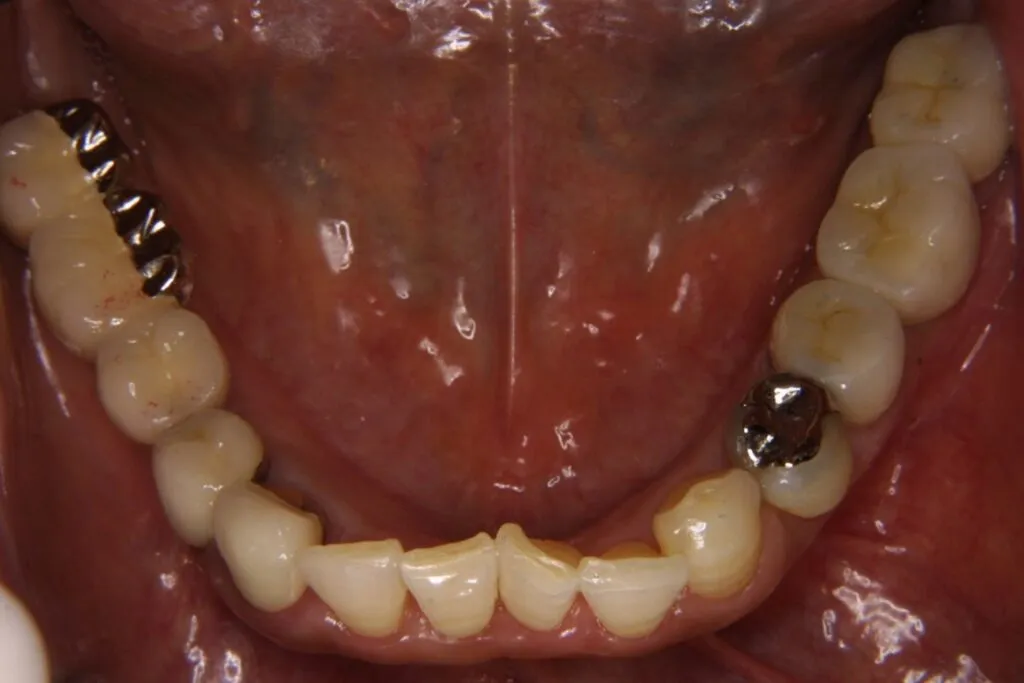

症例⑦

| 主訴 | 残根状態 歯を入れたい |

| 診断名 | 咀嚼障害 |

| 年齢 | 29歳 |

治療に用いた装置(治療法) | インプラント |

| 部位 | 左上6・左上7・左下6・左下7 |

| 治療期間 | 8か月 |

| 治療費用 | 1,848,000円 |

| リスク・副作用(治療に関する) | 腫脹、しびれ |